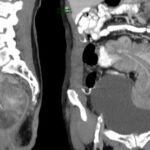

Se presenta el caso de una paciente femenina de 71 años, que ingresa por guardia con dolor abdominal en fosa iliaca derecha y deposiciones diarreicas sanguinolentas. Al examen físico, abdomen blando depresible, con masa palpable, y doloroso a la palpación en FID. En la TC de abdomen y pelvis con contraste oral y EV se observó el pasaje del contraste oral hasta colon derecho. Ángulo derecho descendido de topografía, donde se observa área redondeada de engrosamiento parietal con realce. Distalmente se observa intususcepción, que compromete el resto de colon hasta el recto con ligero realce parietal en dichos segmentos en relación con hiperemia. No se observó dilatación de asas delgadas.

En la TC de abdomen y pelvis con contraste oral y EV se observó el pasaje del contraste oral hasta colon derecho. Ángulo derecho descendido de topografía, donde se observa área redondeada de engrosamiento parietal con realce. Distalmente se observa intususcepción que compromete el resto del colon hasta el recto, con ligero realce parietal en dichos segmentos en relación con hiperemia. No se observa dilatación de asas delgadas.